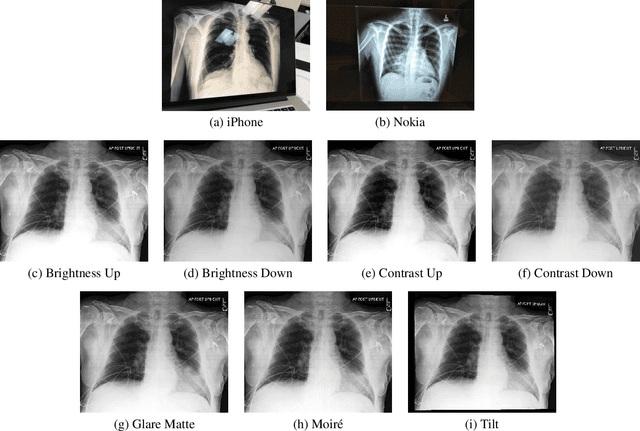

Abstract:Clinical deployment of deep learning algorithms for chest x-ray interpretation requires a solution that can integrate into the vast spectrum of clinical workflows across the world. An appealing solution to scaled deployment is to leverage the existing ubiquity of smartphones: in several parts of the world, clinicians and radiologists capture photos of chest x-rays to share with other experts or clinicians via smartphone using messaging services like WhatsApp. However, the application of chest x-ray algorithms to photos of chest x-rays requires reliable classification in the presence of smartphone photo artifacts such as screen glare and poor viewing angle not typically encountered on digital x-rays used to train machine learning models. We introduce CheXphoto, a dataset of smartphone photos and synthetic photographic transformations of chest x-rays sampled from the CheXpert dataset. To generate CheXphoto we (1) automatically and manually captured photos of digital x-rays under different settings, including various lighting conditions and locations, and, (2) generated synthetic transformations of digital x-rays targeted to make them look like photos of digital x-rays and x-ray films. We release this dataset as a resource for testing and improving the robustness of deep learning algorithms for automated chest x-ray interpretation on smartphone photos of chest x-rays.